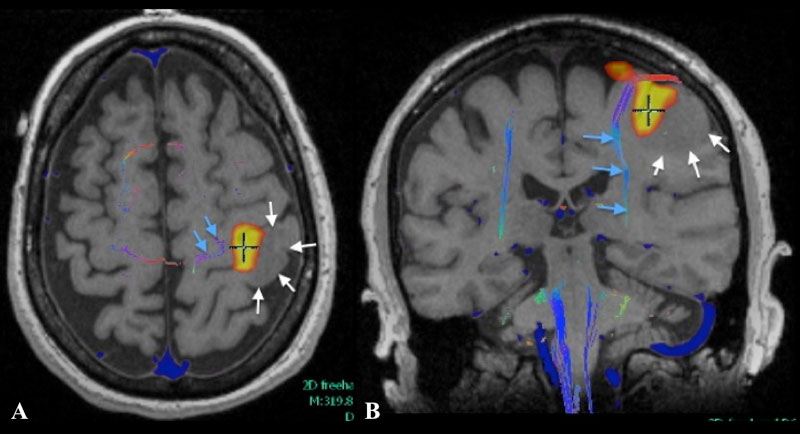

Axial (A) and coronal (B) T1 weighted MR fMRI localizing hand function with relation more laterally placed hypo-intense neoplastic process (white arrows) with more medially situated descending motor fibers of cortico-spinal tract as indicated by MR tractography.